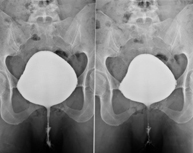

La urografia intravenosa (UIV) consisteix en l'obtenció d'imatges radiològiques seriades del ronyó, vies urinàries i bufeta. Aquest estudi requereix sempre l'ús d'un contrast iodat. - Cistografía (CUMS)

La cistouerotrografia miccional seriada consisteix en l'obtenció d'imatges radiològiques per valorar l'anatomia i la funció de la uretra i la bufeta amb l'administració de contrast iodat a través d'una sonda vesical. - Uretrocistografia (Uretro-Cums)

La uretrocistrografia retrògrada i miccional consisteix en l'obtenció d'imatges radiològiques per valorar l'anatomia i la funció de la bufeta i de la uretra. S'aplica material de contrast a través d'una petita sonda que es troba a la uretra i s'obtenen imatges durant l'ompliment i el buidatge de la bufeta. - Pielografia ascendent per catèter